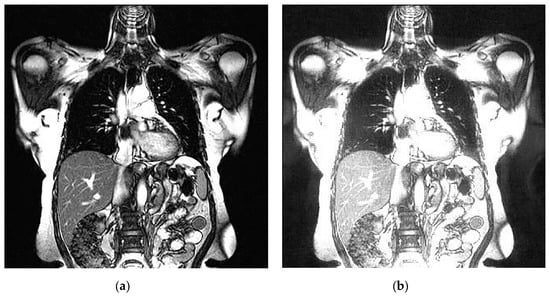

An example of 3D tomographic images “wmri”, “Trufi_COR” and “Body_1.0” DWT with wavelet is shown in Figure 5, Figure 6 and Figure 7 respectively. Frames in Figure 6 and Figure 7 are selected to illustrate the error effect on the image processing result. Figures show a gradual improvement in the quality of processing with an increase the bit-width : in Figure 5b, Figure 6b and Figure 7b visible distortion (Figure 5b is darkened in places, and Figure 6b and Figure 7b are lighted); in Figure 5c, Figure 6c and Figure 7c processed images are indistinguishable by eye from the original images; in Figure 5d, Figure 6d and Figure 7d processed images are identical to the corresponding originals. Experimental results are of higher quality compared with the calculation results. The values dB and at and respectively (Figure 5) obtained after 8-bit image “wmri” DWT with wavelet exceed the corresponding calculated values dB and at and respectively (Table 1). The values dB and at and respectively (Figure 6) obtained after 12-bit image “Trufi_COR” DWT with wavelet exceed the corresponding calculated values dB, dB at and respectively (Table 2). Similarly, for “Body_1.0”.

Figure 5.

Example of 3D tomographic 8-bit image “wmri” DWT by wavelet: (a) original image; processed image: (b) , dB; (c) , dB and (d) , .